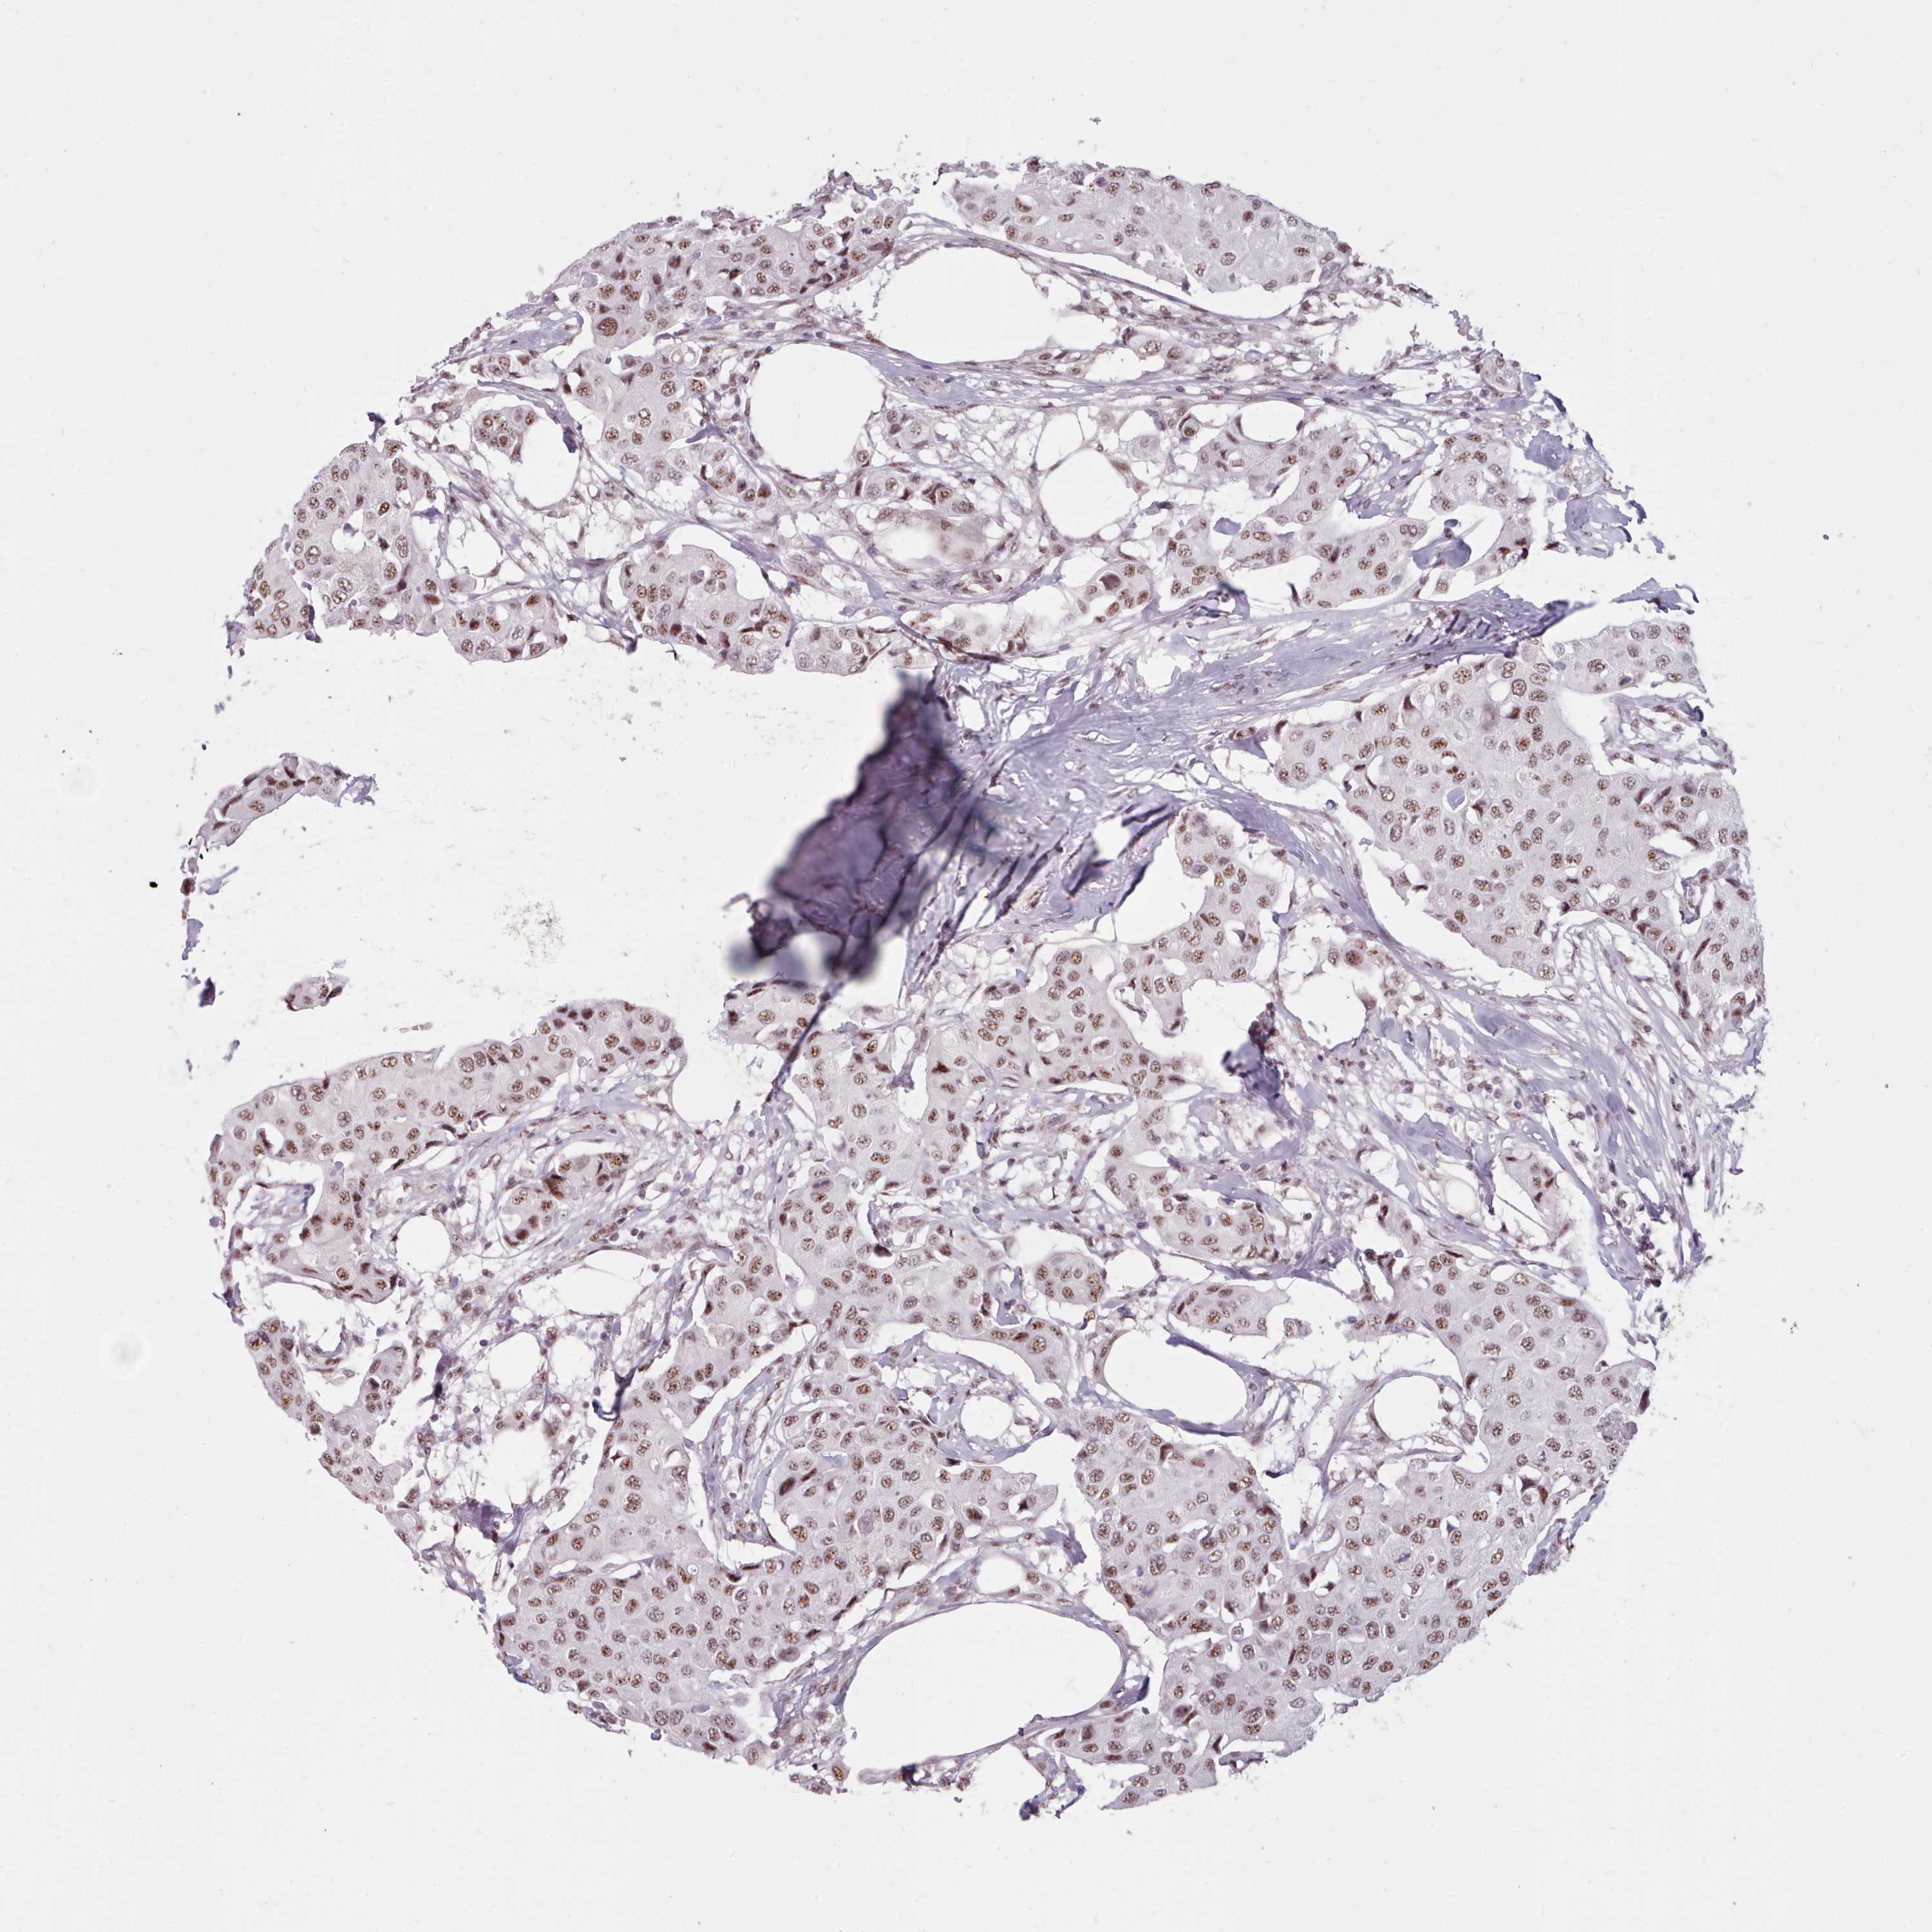

CANCER BREAST CANCER Show tissue menu

BRCA TCGA BRCA VALIDATION PROTEIN EXPRESSION